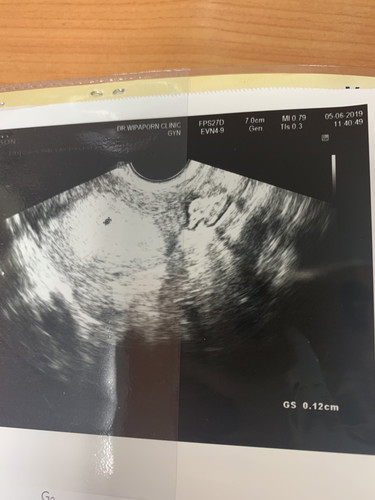

ถุงตั้งครรภ์เล็ก

ไปพบคุณหมอเป็นครั้งแรก หลังจากตรวจขึ้นสองขีด คุณหมอคำนวณจากปจด.ครั้งสุดท้าย ได้อายุครรภ์ประมาณ 6 week(ประจำเดือนมาแต่ไม่ตรงรอบทุกเดือน) เป็นไปได้มั้ย 1)ไข่จะฟ่อ เพราะถุงตั้งครรภ์หมอบอกเล็กมาก แค่ 1 mm. 2)ไข่ตกช้า เลยเจริญเติบโตช้า กังวลมากๆเลยค่ะ กลัวไม่มีการเจริญเติบโต หมอนัดซาวน์อีก2อาทิตย์ค่ะ จิตตกมากๆ?

สอบถามหน่อยค่ะถุงตั้งครรภ์เล็กไปไหมค่ะ6wเเต่คิดว่าหน้าจะไม่ถึงค้ะ